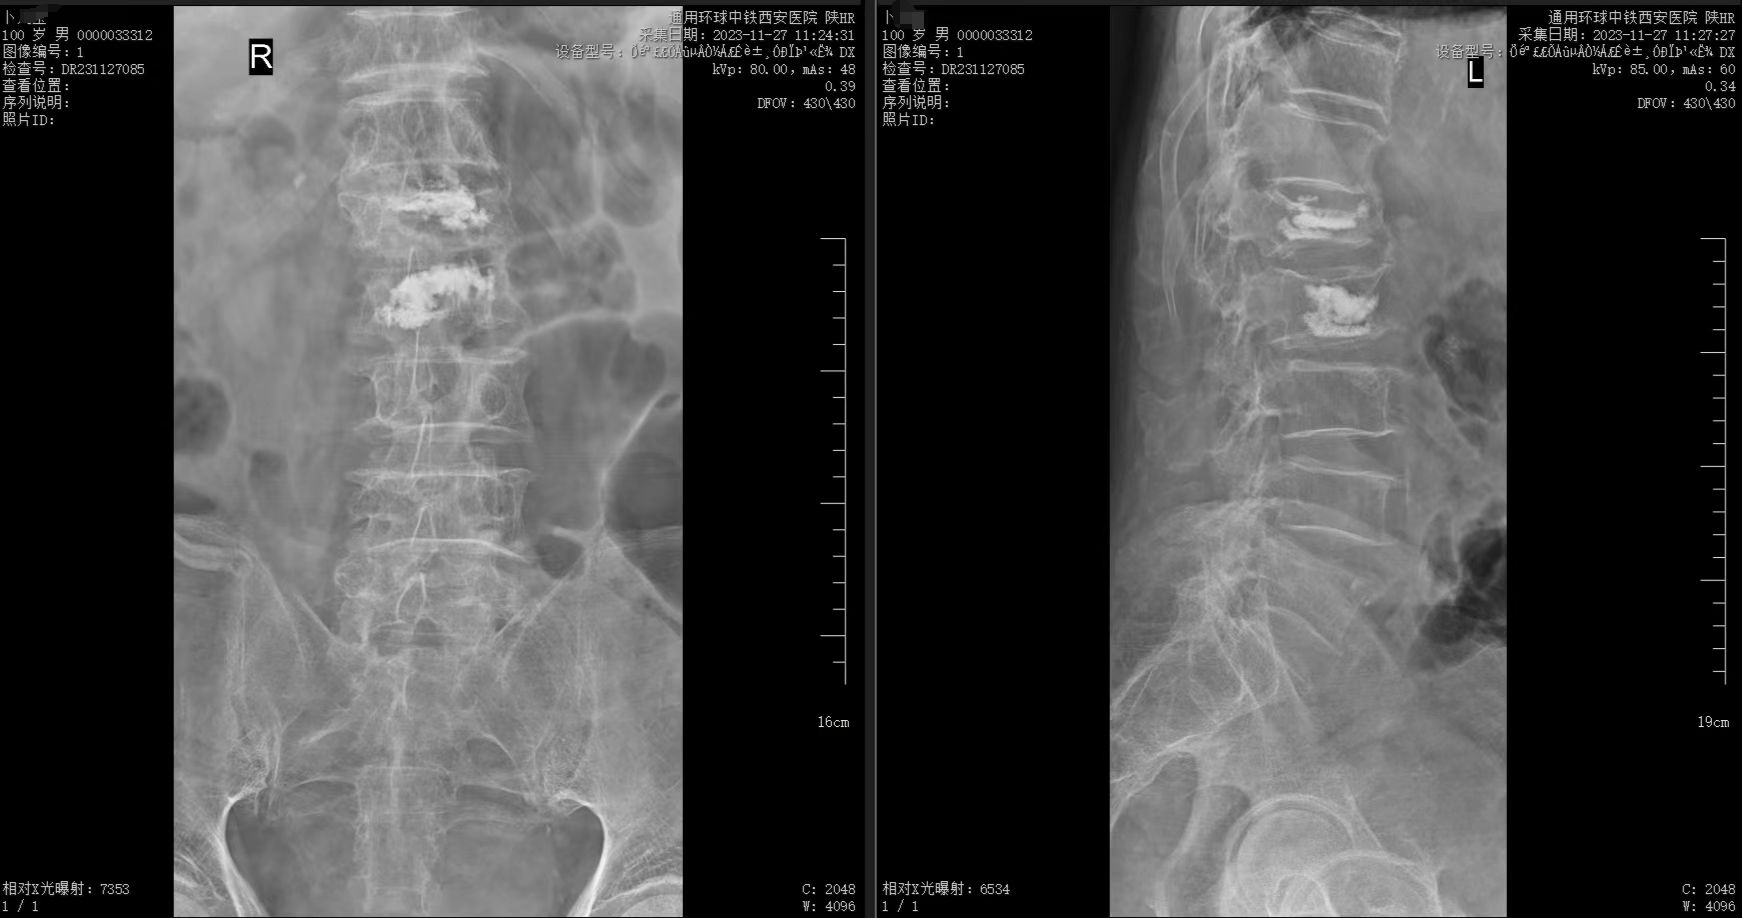

經過周密的術(shù)前準備,姬傳磊團隊憑借豐富的經驗和娴熟的技術(shù),成功爲老人(rén)實施了腰1、腰2椎體(tǐ)新鮮壓縮性骨折經皮骨水泥填塞、椎體(tǐ)成形術(shù)。術(shù)後,老人(rén)安返病房(fáng),生(shēng)命體(tǐ)征平穩,在醫護人(rén)員(yuán)的精心照(zhào)料下,老人(rén)第二天就(jiù)可(kě)以佩戴腰圍坐(zuò)立和下床活動。

術(shù)後影(yǐng)像